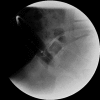

Management of rectal foreign bodies: description of a new technique and clinical practice guidelines

A number of techniques have been described to remove rectal foreign bodies. In this report, a novel endoscopic technique using a pneumatic dilatation balloon normally used in achalasia patients is presented. In addition, a systematic review of the literature was performed for non-operative methods to remove foreign bodies from the rectum. These results are summarised, presented as a practical at-a-glance overview and a flow chart is offered to guide the clinician in treatment decisions. The design of the flow chart was based on the aims to treat the patient preferably on an outpatient basis with minimally invasive techniques and if possible under conscious sedation rather than general anaesthesia.